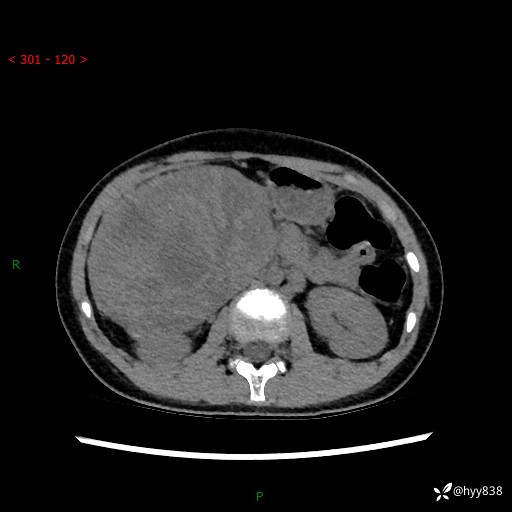

性别:女

年龄:13岁

简要病史:超声提示上腹部巨大包块

上腹部CT平扫